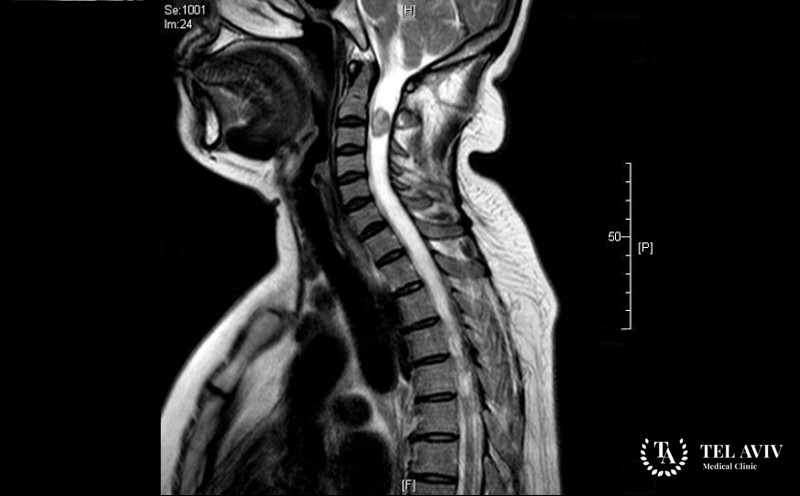

Диагностика и лечение неврилеммомы в Tel Aviv Medical Clinic

Ранняя диагностика и адекватное лечение, которое назначат врачи нашей клиники, обуславливают благоприятный прогноз заболевания, низкую вероятность появления рецидивов. Чтобы подтвердить или опровергнуть наличие опухоли позвоночника, специалисты должны провести комплексное обследование, гарантирующее 100% достоверность результата. С применением передового оборудование, которым располагает Tel Aviv Medical Clinic, и уникальных технологий, врачи проведут оценку размеров, формы и локализации опухоли, степень ее прорастания в смежные ткани, сопутствующие нарушения. По результатам диагностики и индивидуальным показателям, таким как состояние здоровья пациента, наличие других болезней, назначается оптимальный график терапии. Для удаления спинномозгового новообразования часто прибегают к традиционному оперативному вмешательству или альтернативной малоинвазивной радиохирургии.